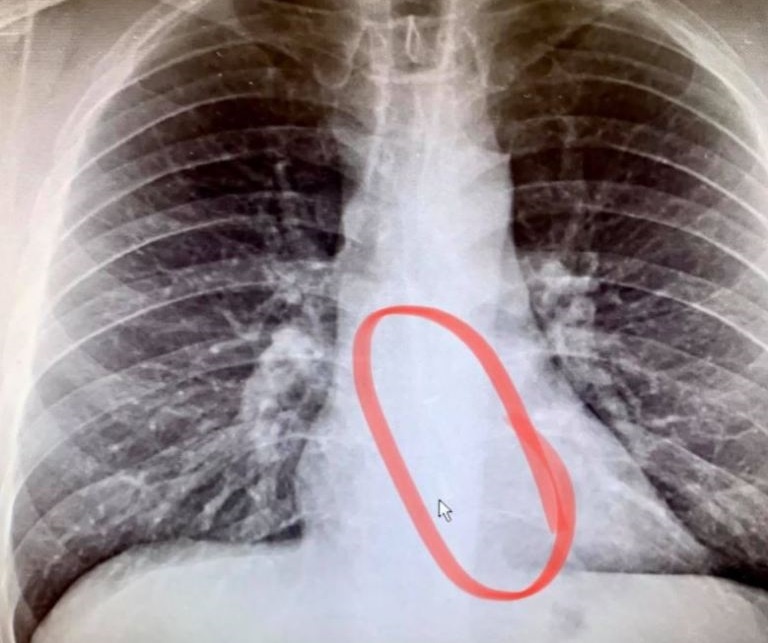

Sau khi chụp X-quang, các bác sỹ xác định chiếc AirPods đã nằm trong bụng Bradford. Ảnh: ValleyCentral.

Gauthier tức tốc đến phòng cấp cứu. Sau khi chụp X-quang, bác sỹ thấy chiếc AirPods bị mất tích mắc kẹt trong thực quản của ông. Các nhân viên y tế thực hiện ca nội soi khẩn cấp, lấy chiếc tai nghe true wireless ra ngoài an toàn, Gauthier không gặp phải sự cố nào khác.